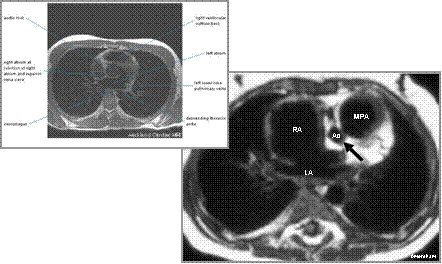

Hypoplastic Left heart Syndrome

Gated spin echo at base of heart shows hypoplastic aorta

(arrow) posterior and right of main pulmonary artery